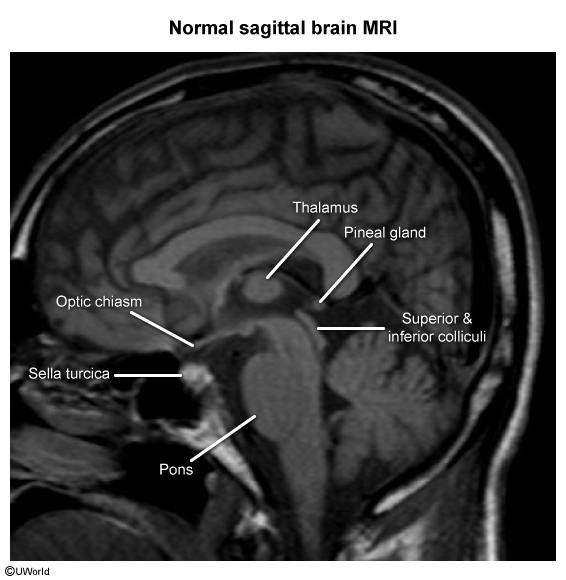

Sagittal section of the brain

Thalamus

The thalamus is a pair of large, egg-shaped gray matter structures in the diencephalon. It acts as the primary relay and processing center for almost all sensory and motor information en route to the cerebral cortex.

- Adult Structures: Thalamus, Hypothalamus, Epithalamus (pineal gland), Subthalamus